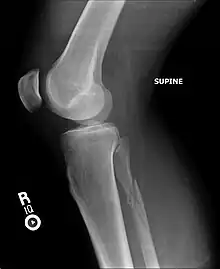

It typically results from excessive external rotation of the ankle.[3] X-rays typically show widening of the ankle joint, though this may be subtle.[3][1] Stress views may be useful in unclear cases.[4] People may not mention pain around the knee due to the greater degree of pain in the ankle.[6] It is classified as a type C3 ankle fracture according to the Danis-Weber classification system.[7]

Ankle Xrays are used to detect widening of the tibiofibular syndesmosis or medial clear space. The medial clear space is the area between the talus of the ankle and the medial malleolus. Damage to the deltoid ligament and syndesmotic ligaments result in mortise instability, causing the talus to laterally shift and widen the medial clear space.[9][16] A study found that the medial clear space size of a normal ankle and an injured ankle measured at 4 millimetres and 5.4 millimetres in length respectively.[14] To confirm diagnosis, full-leg radiographs are used to inspect for fractures of the proximal fibula and widening of the interosseous clear space (or tibiofibular clear space). The interosseous clear space is the area between the medial side of the fibula and lateral side of the tibia. A peer-reviewed study, published in Injury in 2004, found that an interosseous clear space greater than 10 millimetres indicates diastasis of the syndesmotic ligaments.[9]